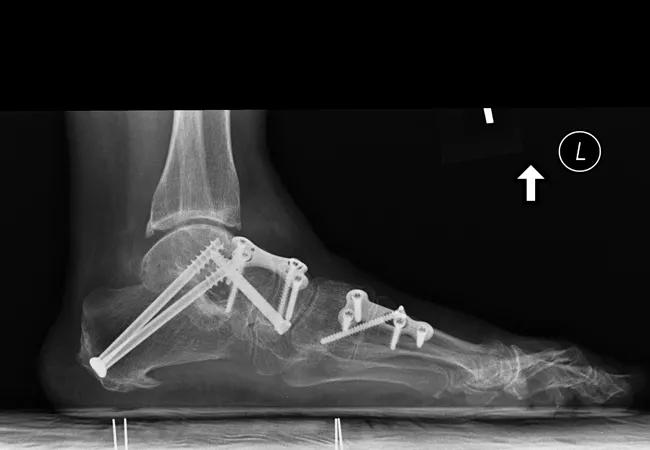

Figure 1. Preop (above) and postop (below) radiographs of a patient who developed tibiotalar tilt postop.

A total of 187 patients were eligible for the study. The average age was 52 (11 to 82) years. The most common indication for surgery was adult-acquired flatfoot deformity (92, 49.2 percent), followed by arthritis (83, 44.4 percent). The most common procedure was a triple arthrodesis (101, 54 percent). A total of 51 patients (27.3 percent) developed valgus tibiotalar tilt postoperatively, at an average time of 3.6 months after surgery (Figure 1).